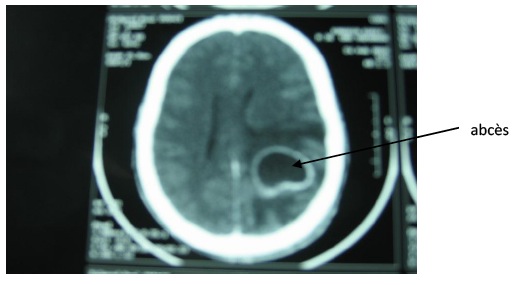

Devant la répétition des convulsions et l’apparition de troubles de la conscience, il est transféré dans un hôpital régional où un scanner cérébral a été effectué Ce scanner cérébral avait mis en évidence un volumineux abcès cérébral pariétal gauche avec un important oedème péri lésionnel et un effet de masse sur le système ventriculaire. Il ne montrait pas de fracture du crâne.

Le diagnostic de l’abcès est posé par le scanner cérébral qui montre un volumineux abcès cérébral de siège pariétal gauche [Figure 1]. Cet abcès est en regard de la plaie du scalp. Il n’y a pas de fracture du crâne. Etonnamment malgré le volume de l’abcès qui parait important, l’état de conscience est resté longtemps conservé voire normal jusqu’au stade ultime de l’engagement cérébral. On note un délai d’environ 3 semaines entre la lésion initiale du scalp et le diagnostic de l’abcès.

La TDM cérébrale avec injection de produit de contraste permet habituellement de mettre en évidence l’abcès cérébral sous la forme d’une hypodensité intra parenchymateuse cérébrale, rehaussée par le produit de contraste. Mais l’aspect peut montrer des nuances selon le stade évolutif de l’abcès [11].